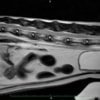

■ MRI検査

第5-6腰椎間で右側神経根が腫大し、脊柱管内に連続した腫瘤病変が認められました。脊髄および馬尾神経は右側から重度に圧迫されていました。

MRI検査所見

MRI 1